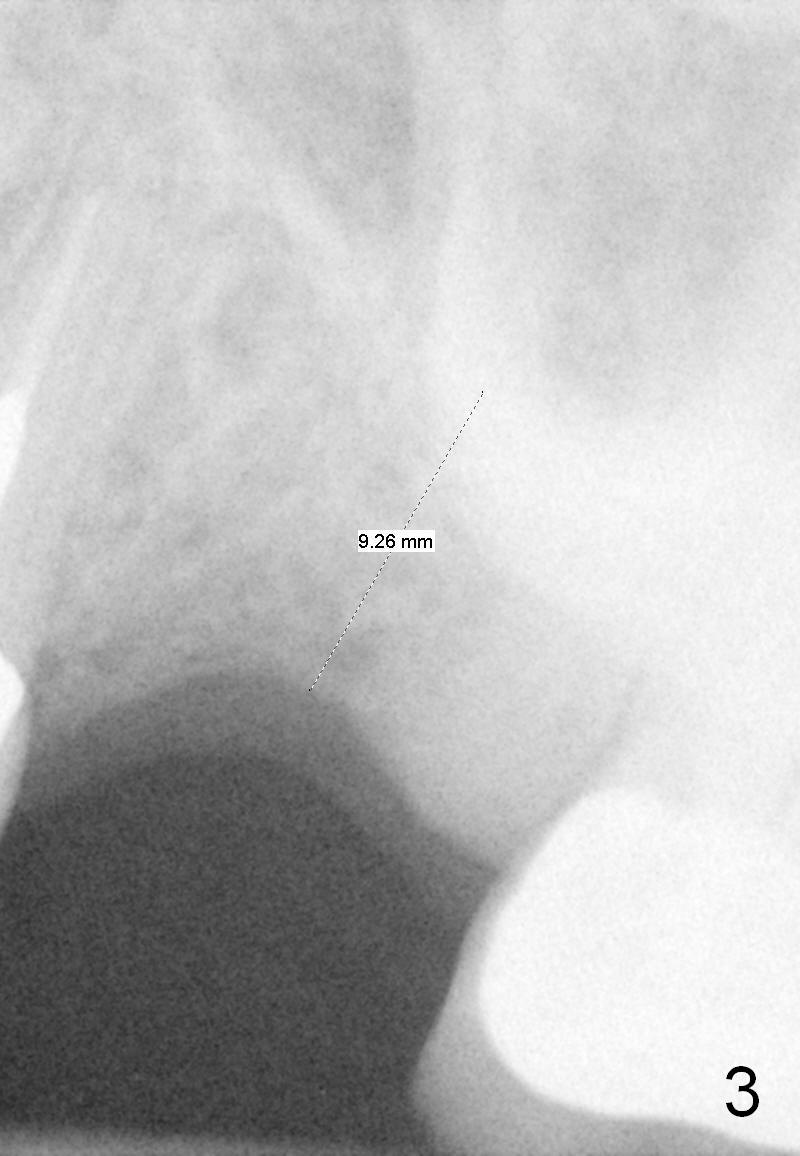

A 58-year-old white woman is afraid of dentistry (Fig1). Two years post extraction of the tooth #14, the bone height reduces by 4 mm (compare Fig.2,3).